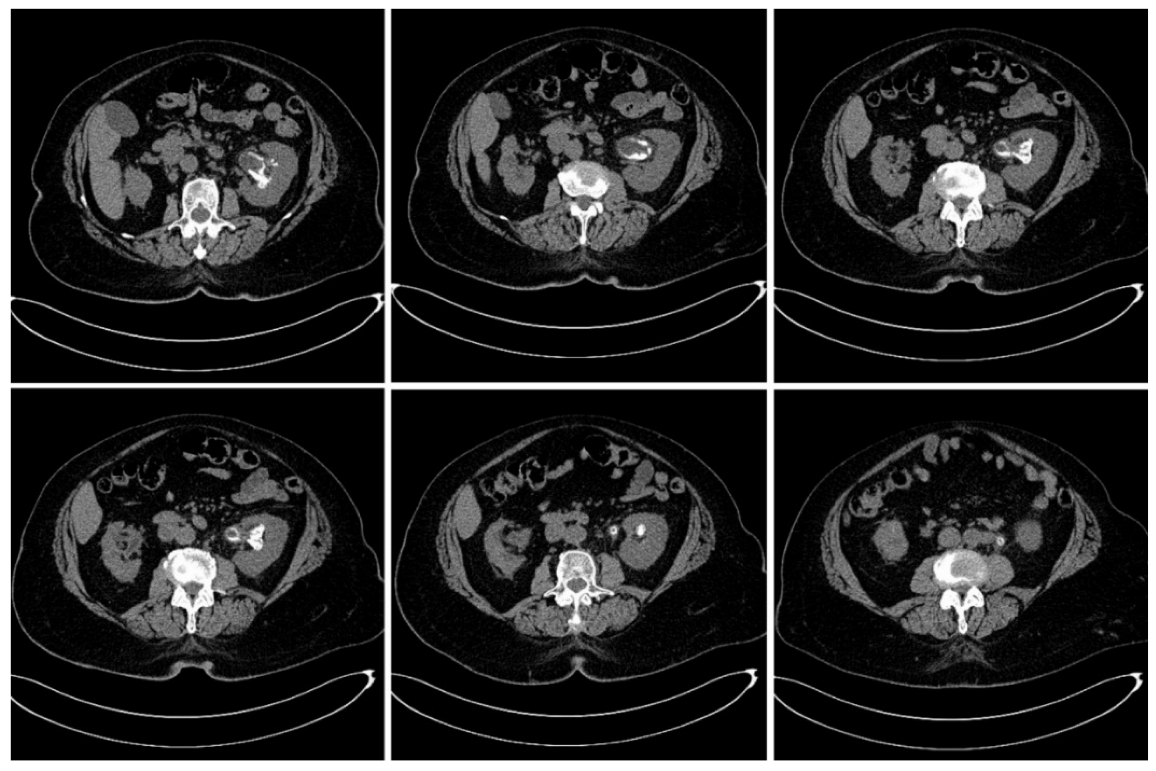

On the sixth week follow-up visit, the general condition of the patient was good, with a complete cessation of the gross hematuria. The hemoglobin level was 9.5 g/dL and kalium level was 5.2 mmol/L; however, renal function did not improve (serum creatinine level was 5.6 mg/dL, eGFR = 8 mL/min/1.73 m2), and consequently, we extracted the double-J stent (which had minimal calcifications at its proximal end) since we considered that it did not cause any improvement in the patient’s renal function. Urine pH was 6.0, and the special CBEU urine culture for Corynebacterium urealyticum was negative. The non-contrast abdominal CT scan showed partial regression of the encrustations, and the maximum density of the calcifications had decreased to 390 Hounsfield units. Considering these improvements, oral acidification of the urine with L-methionine was continued (Figure 4).

Figure 4. Three-dimensional reconstruction based on the non-contrast CT examinations of the patient at the moment of diagnosis (A) and on the sixth week follow-up visit (B), with the ureteric stent in place, showing the partial regression of the pyelic and calyceal calcifications, and the complete regression of the upper ureter calcifications.